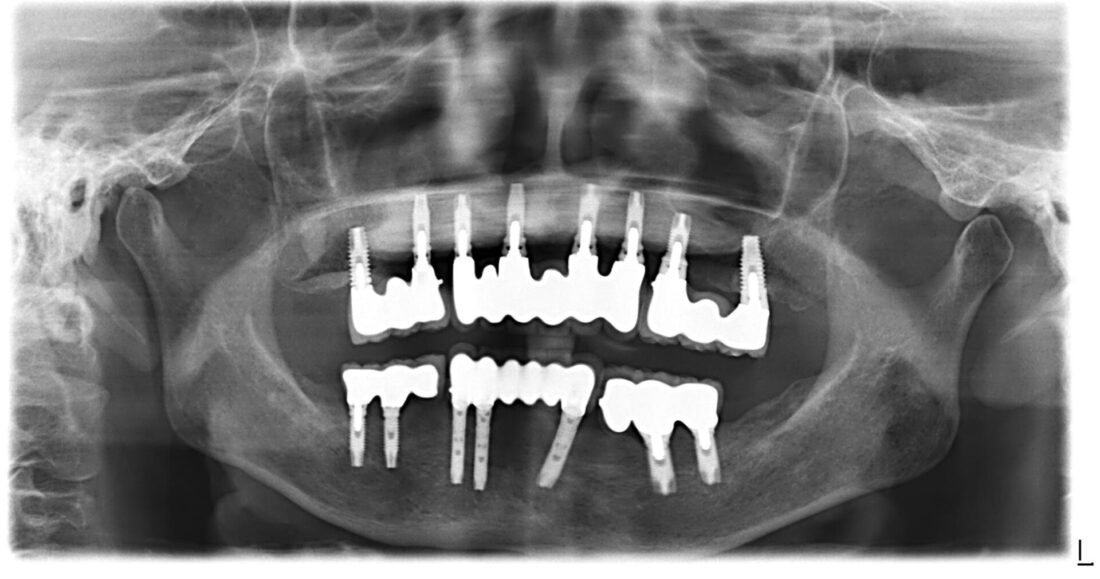

全顎インプラント治療

上下全額にわたりインプラント治療。

治療術後約20年、問題なくメインテナンス中。